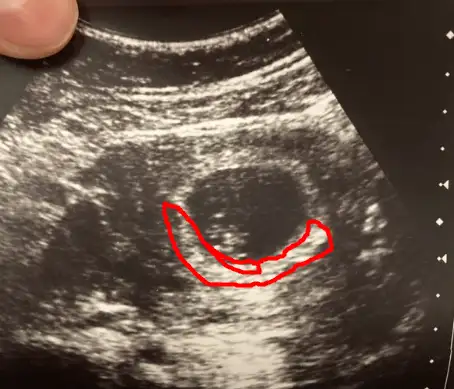

MAŞALLAH CANIM NASIL ÇIKTI HAFATSIYLA UYUMLUMU ? DOKTOR NE DEDİ :)

Bizim seninle aynı canım 8+6 tüp bebek benimde aynı gerginlik bendede sağlıkcakla gelsinler inşallahAmin canım amin hepimizin sonuçları güzel olur inşallah.

Bugün benim kontrolüm var çok korkuyırum kötü bir haber alırım diye belim ağrıyor onun dışında hiç birşeyim yok iyiym ilk başarılı tüp bebeğim olacak inşallah herşey yolundadır hep araftayım Allahım sağlıklı haber almak nasip olur inşallah. 8+6 bugün çok korkuyorum kalbi durmuş haberini alırız diye. Rabbim bizlere herşeyin hayırlısını nasip etsin sağlıkla evlatlarımızı kucağımıza almak nasip olsun.